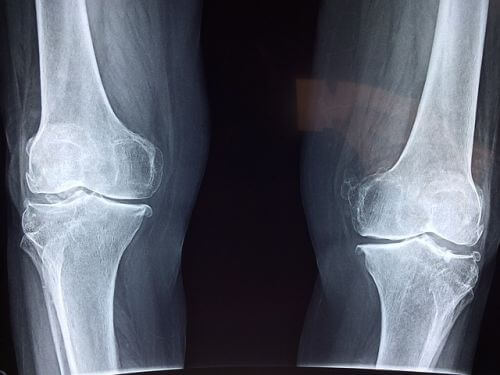

류마티스 관절염의 병리학적 특징은 활막의 염증과 증식, 국소적인 골미란과 관절연골이 얇아지는 것입니다. 만성적인 염증인 활막 표면과 판누스(pannus)를 형성합니다. 지속적으로 활성화된 류마티스 관절염은 관절연골, 뼈를 파괴하고, 이로 인한 기능 장애를 일으킨다. 전신 질환으로, 피로, 피하결절, 폐 침범, 삼막염, 말초 신경병증, 혈관염, 혈액학적 이상 등 다양한 관절 외 증상이 발현됩니다.

류마티스 관절염의 증상은 먼저 손에서 나타납니다. 손가락손허리뼈와 몸 쪽손가락관절에 침범하지만, 질병 후기에는 먼쪽 손가락관절에도 침범될 수 있습니다. 류마티스관절염이 진행되면서, 손이 변형이 일어나서 손가락손허리뼈는 척골편위가 발생하고, 백조목 변형 및 단추구멍 변형이 나타날 수 있다. 또한, 건초염 혹은 건막의 결절에 의한 방아쇠 손가락이 유발될 수 있고, 심한 경우 건파열이 생기며 4.5번째 수지의 신전부에서 가장 호발합니다. 류마티스관절염의 팔꿈치관절의 활막염은 류마티스환자의 50%에서 관찰된다. 팔꿈치에서의 구축도 잘 오지만, 환자는 잘 모를 수 있으니 주의가 필요합니다.